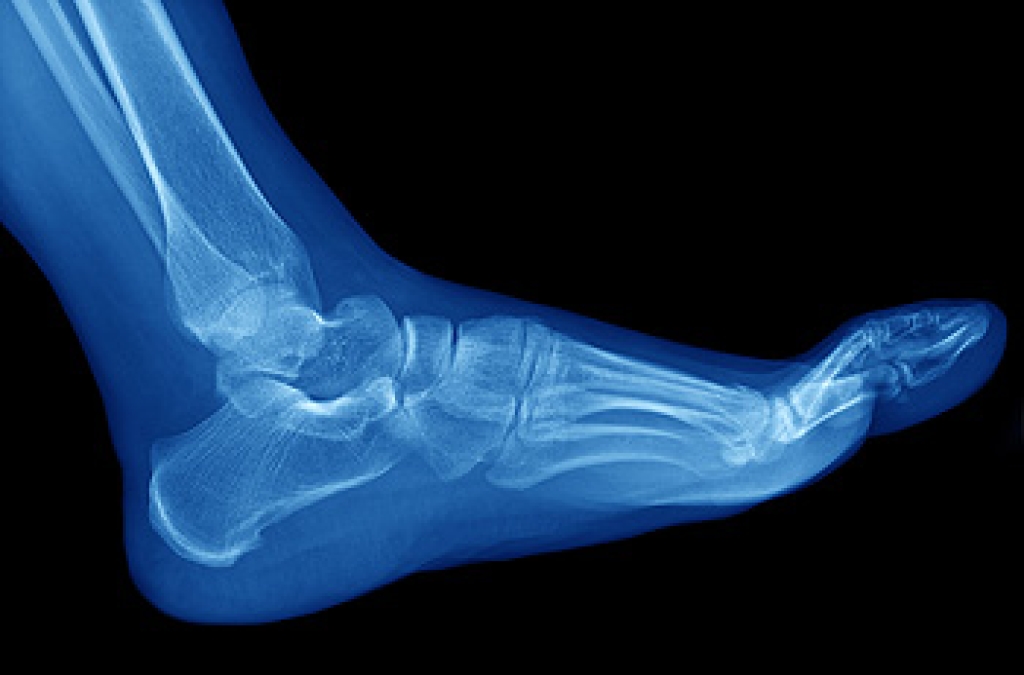

Ingrown Toenails

Ingrown toenails occur when a toenail grows sideways into the bed of the nail, causing pain, swelling, and possibly infection.